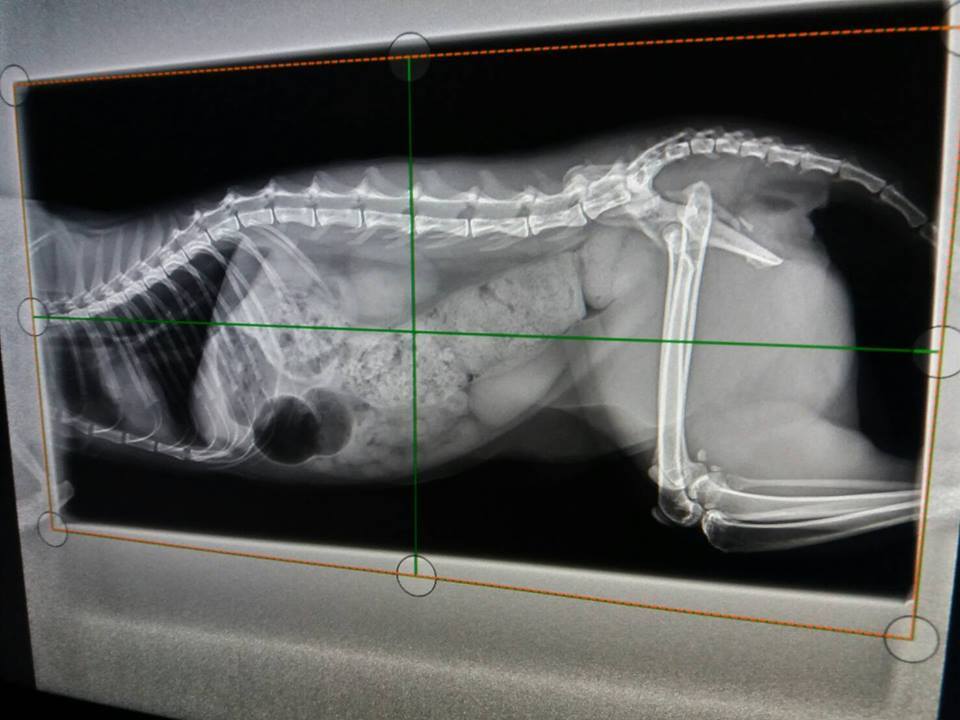

主題: 骨盆腔狹小進行灌腸與追蹤治療的艾咪 申請者姓名: 臺北市支持流浪貓絕育計劃協會 花色: 申請日期: 2017-06-15 11:28:56 申請者部落格: 申請者臉書網址: 所在縣市/合作醫院: 台北市/澄諾動物醫院 治療費用: 6300元 需求人數: 15人 已結案 (2024-06-01 13:27:02) 報名人員: 海郁(已付款)、ocean(已付款)、琪芳(已付款)、林妮妮(已付款)、COCO(已付款)、Jin(已付款)、Karen Chiou x2(已付款)、Tsai Dobbie x2(已付款)、meemee(已付款)、貓步小姐(已付款)、yushi0304 x3(已付款)、 候補人員: 動物病情說明: 因骨盆與腿部骨折而導致骨盆狹小的艾咪,

4/27 澄諾回診 艾咪 3.21KG

【回診狀況】

艾咪又連續沒大便因而再度回診,

X光下發現大腸寬度變大,

認為有一可能導致艾咪雖有大便但無便意,等到積很久後,

後面大便已乾,

認為杜化液可能對艾咪已無太大效果

本日增加軟便劑劑量

且從今日起杜化液提高為5CC,早晚各一次,

飲食部分即日起加入洋車前子